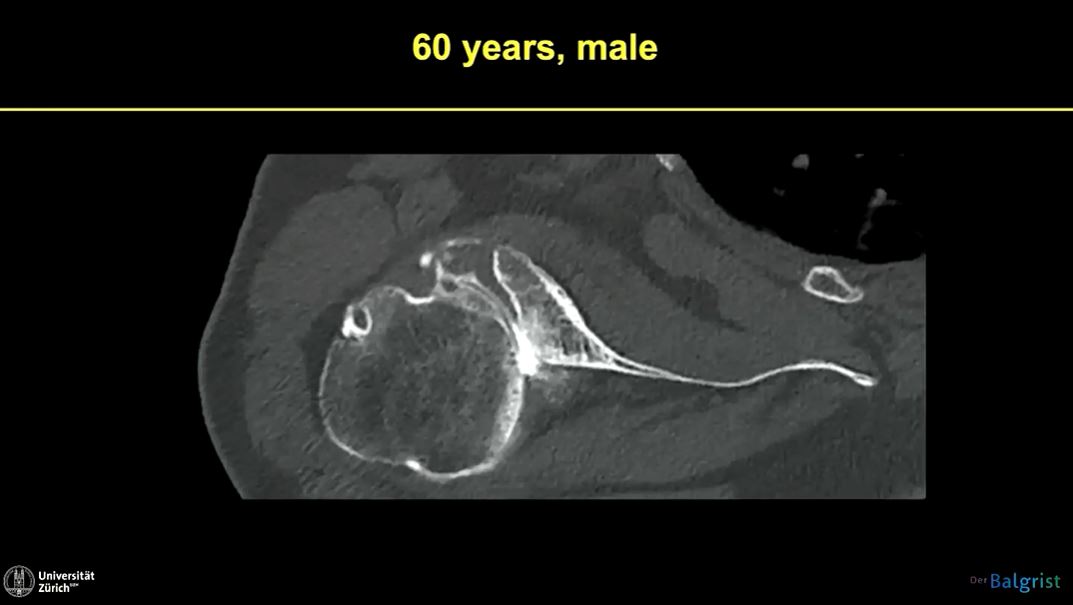

Research enthusiasts watch out! We are excited to present our Winglet Journal Club partner edition in cooperation with Enovis, focusing on the publication "Clinical and Radiologic Outcomes of Lima ProMade Custom 3D-Printed Glenoid Components in Primary and Revision Reverse Total Shoulder Arthroplasty with Severe Glenoid Bone Loss" (Rashid et al., 2023).

Episode #022 | Are Custom Components in RTSA Improving Patients' Outcomes?